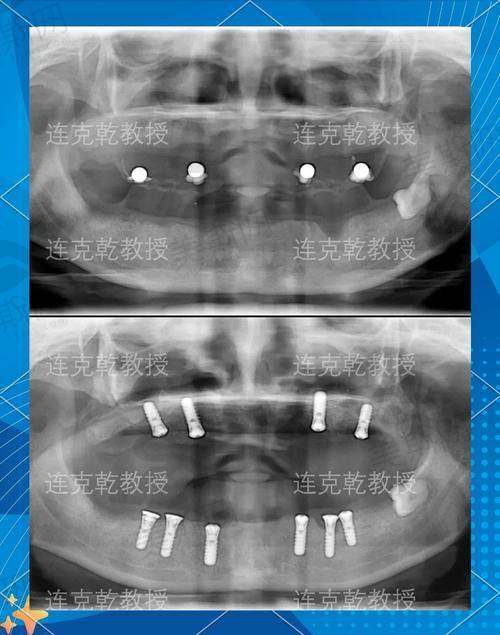

上海鼎植口腔在种植修复领域有着极高的认可度。其创办人及总监华、黎强等都是业界种植修复大拿,他们丰富的经验和不错的技术为医院的种植牙项目提供了坚实的保护。该医院主打种植牙项目,开设的种植牙技术十分齐全,除了常见的单颗、多颗种植外,还擅长即刻种植牙、数字化种植牙、allon4/6即刻负重种植、VIIV穿颧穿翼等疑难种植。

1. 种植技术:上海鼎植口腔主打种植牙项目,开设种植牙技术齐全,擅长即刻种植牙、数字化种植牙、allon4/6即刻负重种植、VIIV穿颧穿翼等疑难种植。上海松丰齿科传承相关口腔技术,在种植修复等方面有竞争力。上海牙博士口腔医院在口腔种植修复、疑难全口义齿修复等方面技术十分出众。